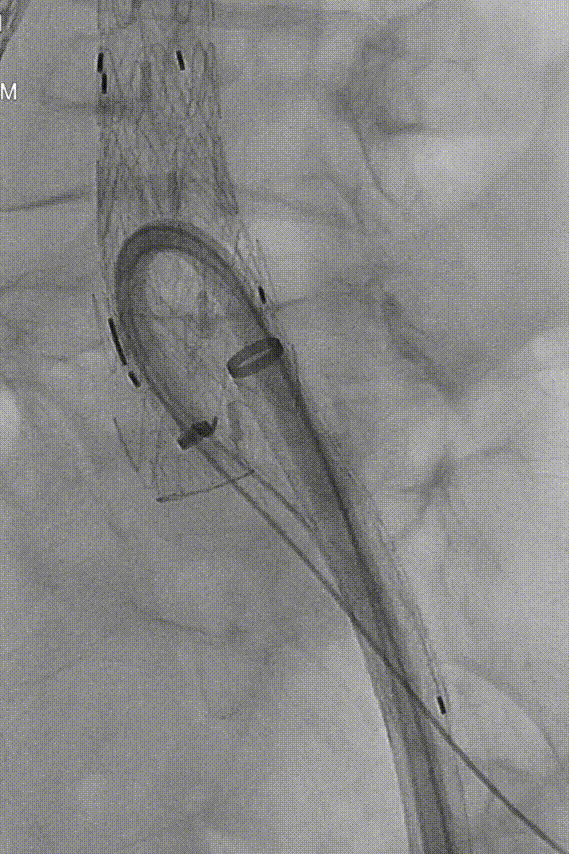

接下来处理左髂Ib型内漏,拟采用IBE支架内同侧翻山完成修复。于左股动脉内预置两把Proglide后,交换Amplatze导丝及GORE 20Fr鞘。沿导丝导入GORE腹主动脉覆膜血管内支架主体(PLC201000,16mm-20mm-95mm),近端支架覆膜部分重叠原左侧髂动脉分支释放。

gore医疗怎么样「漫腹精论」独具匠心 推陈出新——同侧IBE支架内翻山重建髂内动脉治疗EVAR术后内漏病例报道_https://www.jmylbn.com_新闻资讯_第13张

释放髂支

保留Amplatz导丝,于体外将260cm软泥鳅导丝置入GORE髂动脉分支型覆膜血管内支架CEB231010(23mm-10mm-100mm)中,形成牵张通道,沿GORE 20Fr鞘植入IBE主体支架,退鞘至短腿下方,于目标位置释放至短腿打开,再次退鞘至长腿远端,释放IBE主体支架长腿。

gore医疗怎么样「漫腹精论」独具匠心 推陈出新——同侧IBE支架内翻山重建髂内动脉治疗EVAR术后内漏病例报道_https://www.jmylbn.com_新闻资讯_第14张

释放IBE主体到短腿